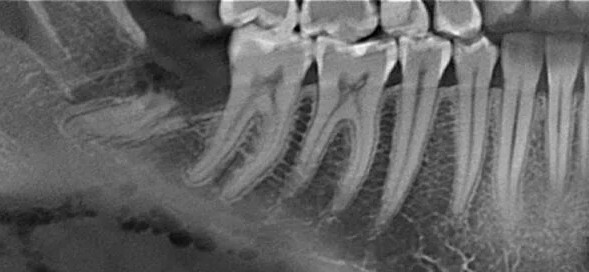

- Диагностика. Первым делом выполняется рентгенологическое исследование (прицельный снимок или КЛКТ), чтобы точно определить положение, количество и форму корней, оценить состояние окружающей кости.